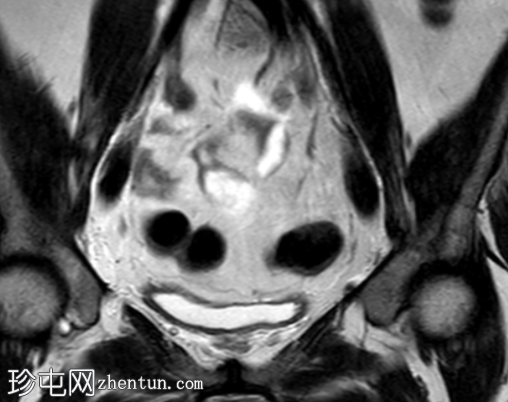

冠状位

T2加权像

盆腔MRI显示左侧骶前区有两个小囊性病变,位于左侧附件的预期解剖位置。

病变在T2加权像上呈高信号,边界清晰,囊壁轻度增厚,光滑。在T1加权脂肪抑制像上,一个病变内部呈高信号,另一个病变呈低信号。静脉注射对比剂后,可见轻度周边囊壁强化,未见强化的实性成分。

未见扩散受限。病灶与邻近盆腔血管关系密切,无周围炎症改变、盆腔淋巴结肿大或游离液体的证据。

在术后盆腔中,MRI 对于病灶的定性尤为有用。典型的影像学特征包括位于预期卵巢解剖位置的囊性或混合性囊实性病变,通常与盆腔血管紧密相邻。常见的影像学特征包括 T2 高信号、T1 信号强度因出血或蛋白含量而异、轻度周边强化以及无扩散受限。